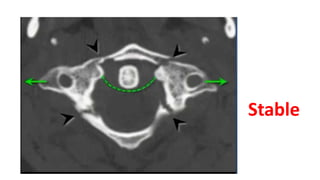

Stable

Rule of Spence

• #37 Any tilt on the neck when the force is being applied

• #39 Motor vehicle crashes falls